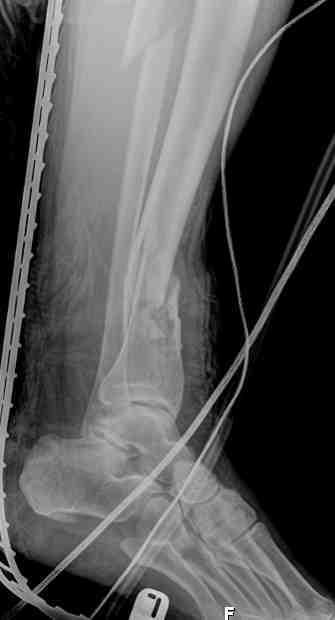

Выше приведены рентгенограммы 13-летнего подростка, страдающего от огнестрельного многооскольчатого перелома дистальной трети бедра. AO наружный фиксатор наложенный в день травмы не дал приемлемой редукции. Через три недели после перелома аппарат Илизарова был наложен без попытки одномоментной репозиции на операционном столе. There are X-Rays of a thirteen year old boy with a comminuted distal femur fracture secondary to a gunshot wound, initially treated with an AO external fixator. The alignment was unacceptable and an Ilizarov external fixator was applied three weeks after the injury. No attempt of definitive reduction was made during the surgery.

Гексаподная приставки наложена на 10 дней и приемлемая редукция была получена. The Hexapod set was applied for ten days and acceptable reduction was received.

По окончанию редукции Гексаподный сет был снят и дальнейшее ведение больного проходило в стандартном режиме аппарата Илизарова. Хороший анатомо-функциональный результат был получен. When reduction was finished, the Hexapod set was removed and further management has been continued by standard Ilizarov regime. Good anatomic and functional results were achieved.